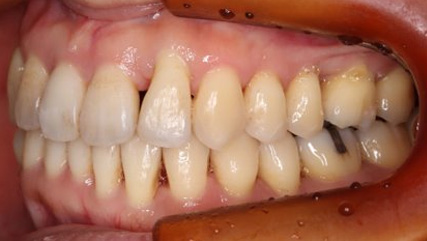

乱ぐい歯、でこぼこがとても酷い状態になります。歯が前後的に重なってしまっている、八重歯になっているなどがこのジャンルに入ります。

顎の大きさと歯の大きさのギャップが大きく、時には歯を抜かないと矯正治療ができない場合もあります。当院では治療期間が長くなるが抜かない治療方針など、一つの治療プランだけでなく、さまざまな可能性の治療方針を説明させて頂くよう心掛けております。こういった考え方はインフォームド・チョイスと言われ近年大切にされている考え方と言われております。

治療前

治療終了前